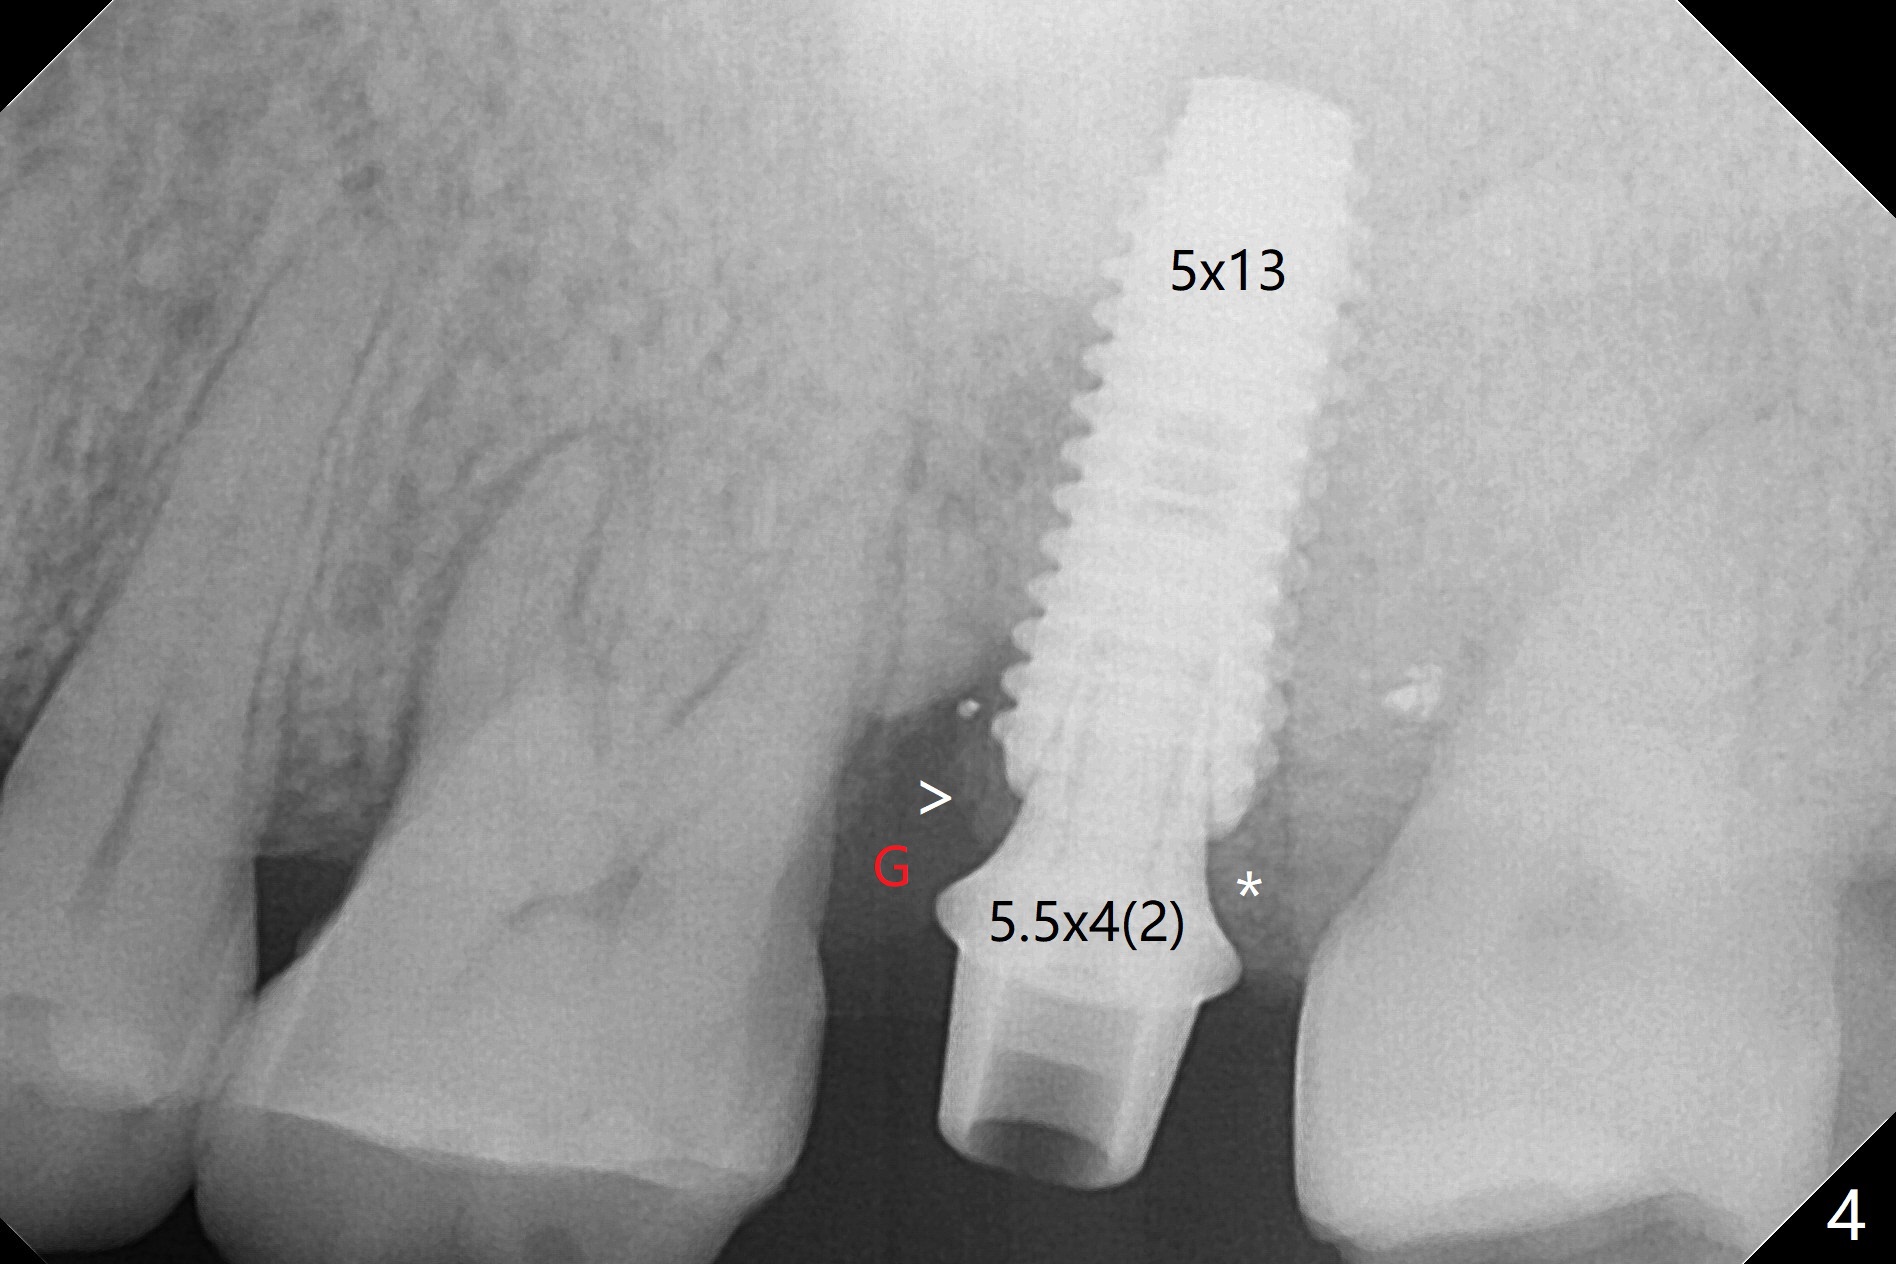

When the patient returns for the tooth #15 extraction and implant, the mesiobuccal residual root has been expelled, while the distobuccal and palatal roots seem to have extruded (Fig.1). The mesial portion of the gingiva (G) is intact and thick. The trajectory of the initial osteotomy is to be changed as shown by red line in Fig.2. The 3.8 mm drill appears to be distal (Fig.3). With mesial bone removal with Lindamann bur, the position of the final implant (5x13 mm) is within normal limit (Fig.4 (50 Ncm)). Because of the thick mesial gingiva (Fig.4 G) and placement of the 5.5x4(2) mm abutment, insertion of mixture of autogenous and Vanilla Graft (*) into the mesial aspect of the implant is difficult (Fig.4 >). Further pushing of the bone graft from the buccal and palatal socket gaps results in more ideal packing (Fig.5 >). If the bone graft were placed first, packing would have been easier. An immediate provisional is fabricated to prevent further mesial shifting of the 3rd molar (Fig.1 arrow). The implant remains stable, while the provisional and abutment are loose 3 months 1 week postop (Fig.6). Impression is taken after abutment cleaning and retightening. Because of the long implant (13 mm), a permanent crown can be cemented early (3 months 20 days postop, Fig.7).